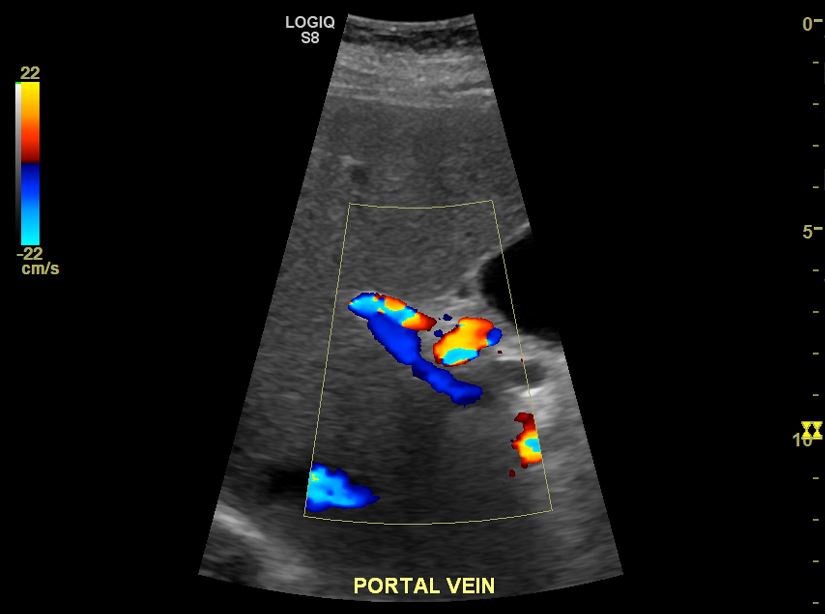

간경변에는 간세포암이 합병되는 경우가 많으므로, 조영제를 사용한 다이내믹 CT·MRI 검사나 초음파 도플러법 등으로 암 조직 내 혈류를 평가하여 암을 진단한다.

간경변에는 간세포 암이 합병되는 경우가 많으므로, 조영제를 사용한 다이내믹 CT·MRI 검사나 초음파 도플러법 등으로 암 조직 내 혈류를 평가하여 암을 진단한다.